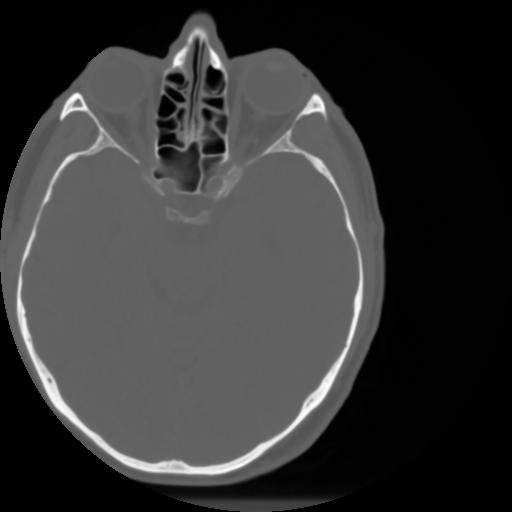

3 CEREBRO,,Axial,3.0,CEREBRO,,